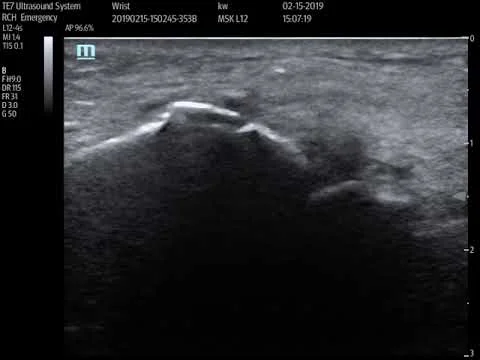

Synovial thickening R wrist